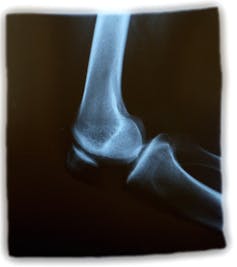

Osteoporosis, a disease of ageing in which a person’s bones become brittle, putting them at high risk of fracture, is generally considered a woman’s disease. That’s because many more women than men have it.

However, both men and women aged over 70 with a clinical diagnosis of osteoporosis and a history of risk factors – such as parent fracture history, certain medications or lifestyle – have a similar high risk of a hip fracture in the next ten years.

This risk is up to 43% chance of hip fracture for men and 47% for women. While the prevalence of hip fractures is higher in women, men have a higher risk of death following hip fracture. The reasons for this are not known.

Risk of fracture in any individual is determined by the influence of the environment, nutrition and genes over their lifetime, which contribute to bone structure. The risk is determined by peak bone mass (which is the maximum amount of bone mass attained at adulthood), bone quality (the distribution of minerals in the bone) and bone loss with ageing.